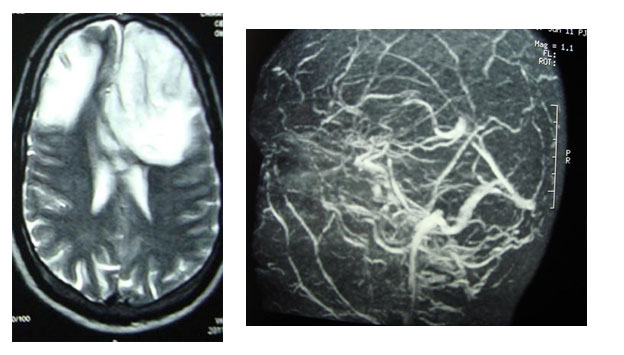

MRI and MRV in a patient with CVT and bilateral frontal venous infarction.